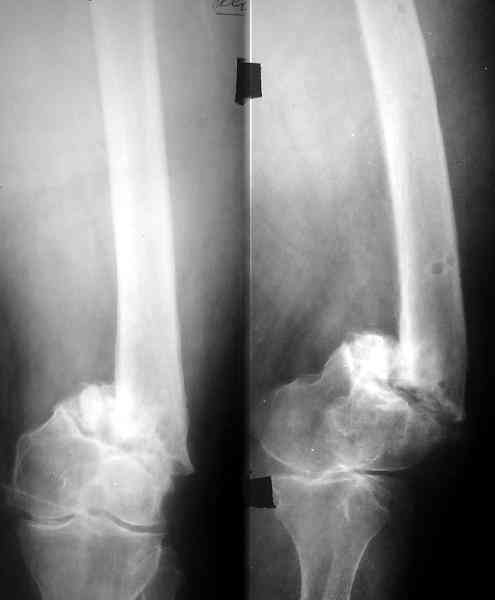

Спасибо. Прооперировали во вторник.

Выглядит красиво. А движения в колене какие были на столе?

Была контрактура и спаянный с суставной поверхностью надколенник. Сделали до синтеза редрессацию. Достигли почти полного объема движений.